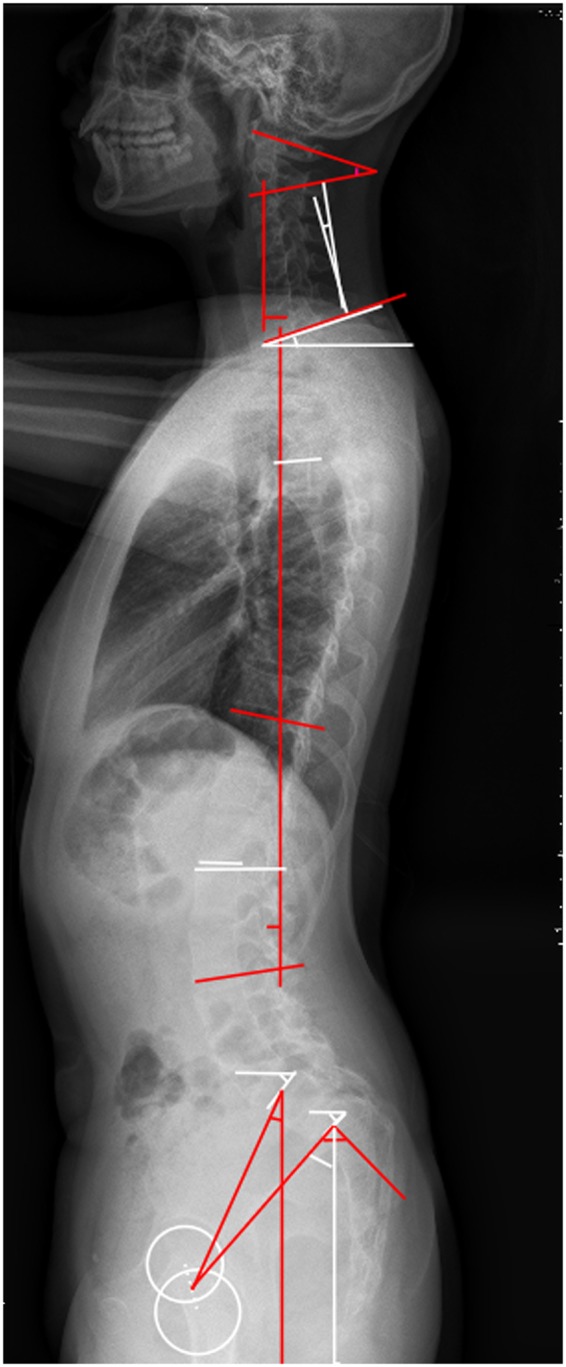

From August 2009 to August 2017, a consecutive group of 29 adolescent patients with lumbar spondylolistheses was reviewed. All patients complained repeatedly of low back pain and were admitted to our department for surgical treatment. Oblique X-ray films or CT images were used to confirm the defects in the pars interarticularis (Fig. 1). For each patient, we selected 2 age-matched, gender-matched, Body Mass Index(BMI)-matched controls who attended the Outpatient Department for scoliosis screening, and were eventually excluded via full spine X-ray films. None of the controls had a history of spinal disorders or spine surgery, nor any history of low back pain and radiologic abnormalities. Moreover, all cases and controls were less than 18 years old. This study was approved by the Institutional Review Board of ChangHai hospital. This study was approved by the Institutional Review Board of ChangHai hospital. Given the fact that all participants were under the age of 18, informed consents were obtained from their legal guardians. We confirmed that all experiments were performed in accordance with relevant guidelines and regulations.

Figure 1.

Demonstrated an adolescent lumbar isthmic spondylolisthesis patient.